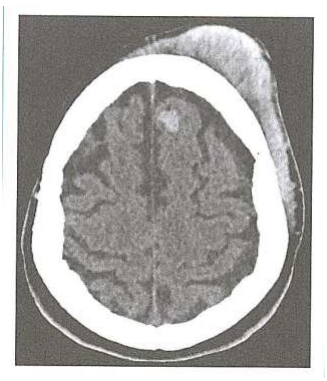

Paciente sexo masculino, 38 anos, deu entrada no PA de um hospital local, vítima de atropelamento ao tentar

atravessar uma movimentada avenida fora da faixa de pedestre. Apresenta-se agitado, com diversas

escoriações pelo corpo e corte extenso na região frontal à direita. Realizados os procedimentos de rotina, foi

solicitado TC de crânio.

Após a análise da imagem, confirma-se que se trata de um hematoma